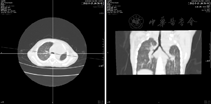

肺未发生和肺未发育的原因目前不清楚,可以累及单侧或双侧,以单侧为常见,左侧较右侧多见。双侧受累出生后无法存活,单侧受累患儿可无症状或有轻到中度呼吸困难,也可有反复肺部感染,也可无症状至成年。约50%同时伴其他系统畸形,如心血管(动脉导管未闭等)、胃肠道(气管食管瘘、肛门闭锁)、泌尿系统或骨骼畸形。产前超声检查很难发现肺未发生和肺未发育,纵隔移位可能提示诊断。出生以后肺未发生和肺未发育的胸片改变一致,均为患侧肺野密度均匀增高,心脏、纵隔向患侧移位,健侧肺透亮度增加,体积增大和肺纹理增粗,横膈低平,可有纵隔疝(图1A)。肺CT检查可以帮助确定患侧有无肺实质、支气管和肺动脉的存在(图1B)。据此可以鉴别肺未发生(无支气管)还是肺未发育(有部分支气管)。有资料显示肺未发生和未发育的病死率约为50%,其预后主要取决于是否合并其他异常,特别是心脏异常,另外发生于右侧的预后较左侧差[3]。

注:A:胸片示右肺实变,纵隔明显右移;B:胸部CT平扫及心脏CT增强示右肺、右肺动静脉未见显示,心脏右移伴逆时针方向转位,右肺动静脉缺如 A:Plain radiographs show consolidation of right lung with ipsilateral mediastinal shift;B:CT scan and cardiac CT angiography images reveals complete absence of right pulmonary vasculature,and the heart moves to the right with coun-ter clock transposition